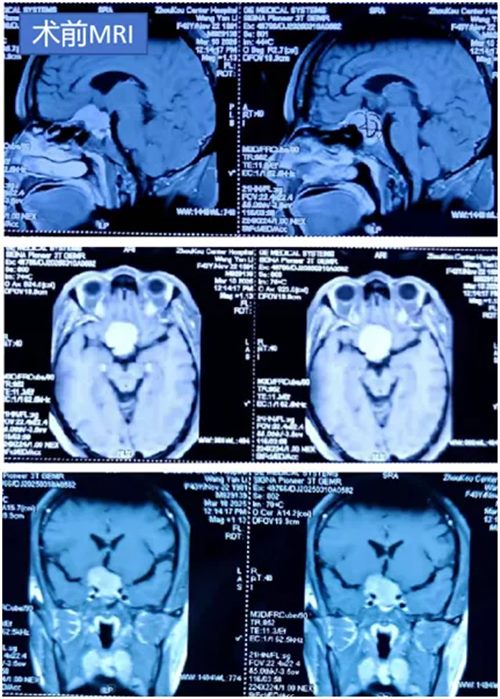

三个月前,王女士右眼急剧下降,伴随的间歇性头痛。MRI显示,一颗直径3cm的肿瘤正疯狂挤压她的鞍区,此处是被称为"脑部十字路口"的险要之地,汇聚着视神经、垂体与颈内动脉。王女士找到马建主任时,右眼视力已基本丧失,左侧视力也日益减弱,不加以控制,可能失明并引发内分泌功能紊乱。

马建主任和周少龙副主任术前详细阅片并在脑海中反复预演手术过程,制定了周密的手术方案,经过2小时精细操作,成功实现肿瘤全切,所有关键神经血管结构毫发无损。术后患者左侧视力得以保留,头痛症状消失,无尿崩、眼球运动障碍等并发症,在鲁小丽护士长带领的护理团队的精心护理下恢复良好,目前已顺利康复出院。